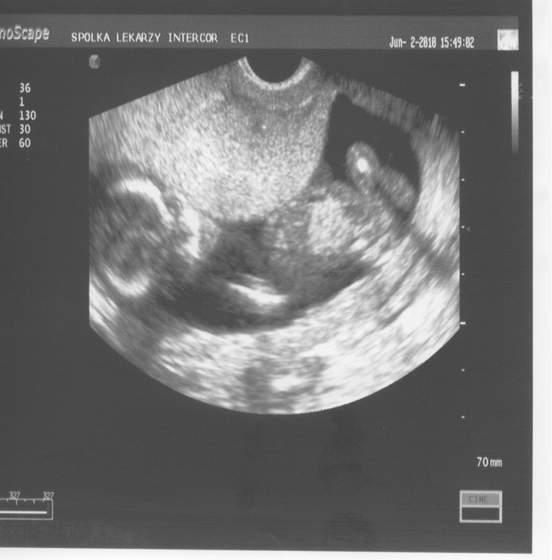

piekna dzidzia ciekawa jestem czyi ja w 13 tygodniu na usg sie dowiem plec tak wstepnieZobacz załącznik 258097

dwie lekararki powoedziały,ze wyglada na dziewczynkę, ale to jeszcze wczesnie jest...